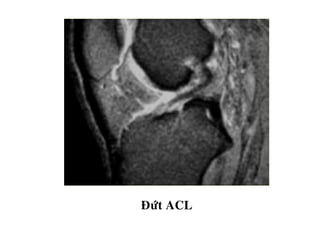

Ñöùt ACL

ĐỨT HOAØN TOAØN ACL

TOÅN THÖÔNG DAÂYCHAÈNG CHEÙO - Daây chaèng coù höôùng ñi baát thöôøng, maát lieân tuïc moät phaàn, coù tín hieäu dòch cao treân T2W beân trong, daây chaèng phuø daøy leân (toån thöông caáp) hay khoâng daøy (toån thöông maïn). - Maát lieân tuïc hoaøn toaøn, khoâng thaáy daây chaèng treân phim.